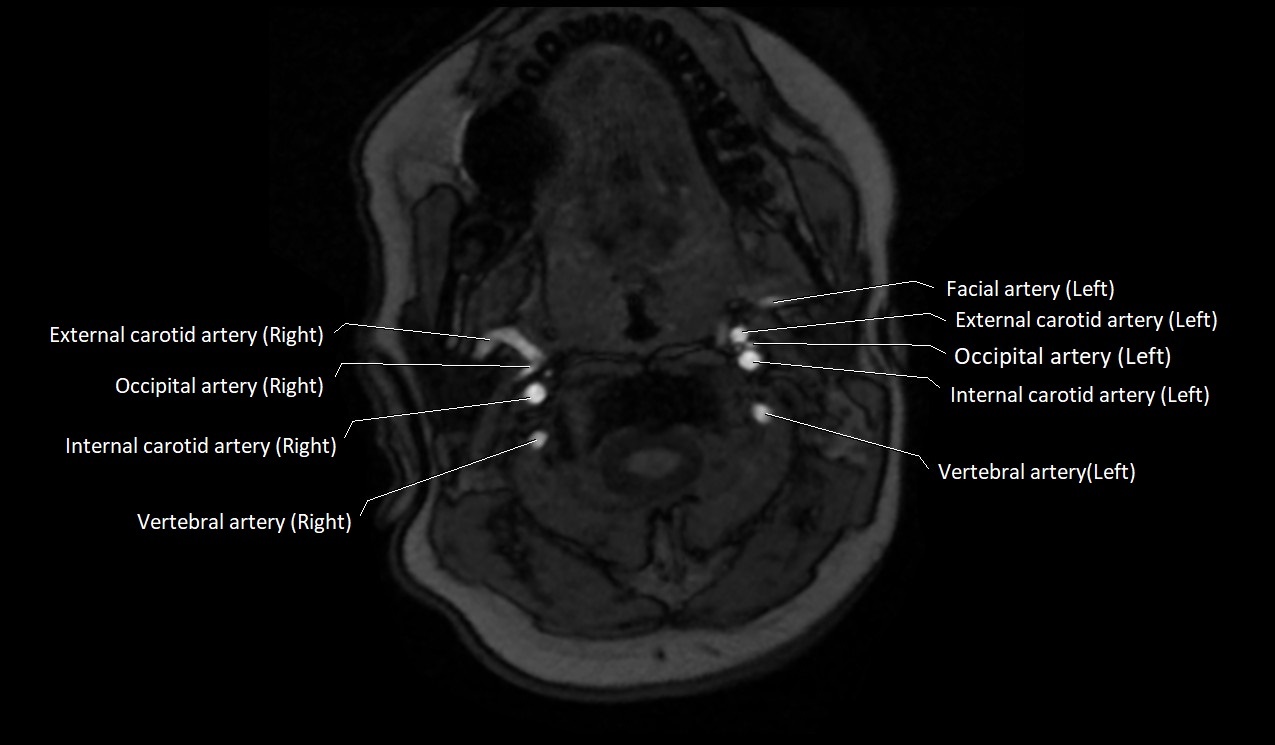

CT image

image